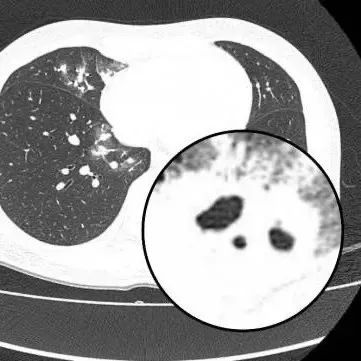

女子干咳一周CT惊现“鬼脸征”,确诊新型隐球菌肺炎,曾圈养鸽子4天后宰杀煲汤!

医生查房时,捕捉到CT上形似“鬼脸”的特殊影像(即“鬼脸征”),并伴有“晕伦征”,高度怀疑隐球菌肺炎。医生追问夏女士近期是否曾接触鸟类、禽类及饲养宠物,夏女士否认。

在影像学表现方面,典型CT表现是单发/多发结节伴“晕轮征”,结节液化坏死可形成空洞形似“鬼脸征”,空洞常为薄壁空洞、无液平。